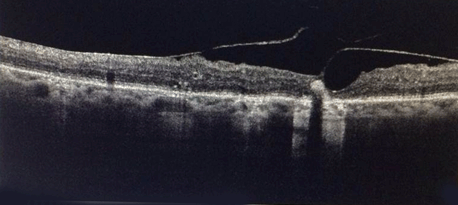

Funduscopic examination at sixth month follow-up revealed a distinct epiretinal membrane which was confirmed by optical coherence tomography (OCT). Fundus fluorescein angiography (FFA) revealed multiple circular scar marks suggestive of laser treatment at macula and foveal region (Figure 1).

Figure 1: Fundus fluorescein angiography revealed multiple circular scar marks suggestive of laser treatment at macula and foveal region.